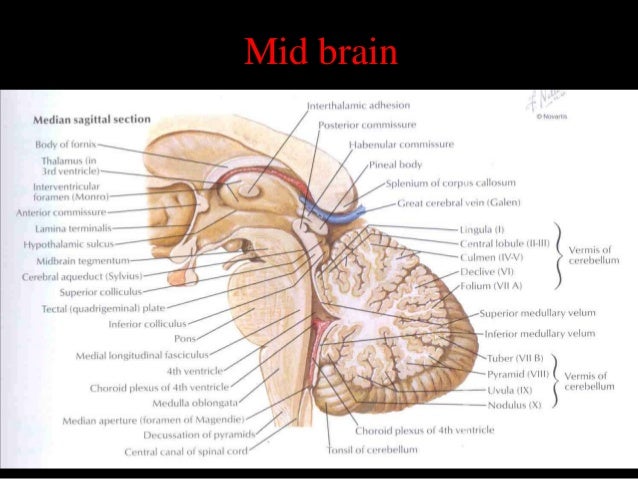

Sectional anatomy of the structures of the brain as viewed with ct mri and pet fusion imaging. It is superior to the upper pole of the right kidney whereas the left adrenal gland is anteromedial to the upper pole of the left kidney.

These labeling exercises are to aid the viewer in learning the sectional anatomy of the brain.

Learn cross sectional anatomy brain with free interactive flashcards. What is the term for the space that exists during fetal development and that disappears in most children during infancy. This video is from our cross sectional anatomy series.

Materials members learning exercises bookmark collections course eportfolios peer reviews virtual speakers bureau. Online mri ct sectional anatomy omcsa k anatomy is probably one of the most user friendly and convenient online interface for human anatomy atlas. Anatomical structures and specific areas are visible as interactive labeled images.

Mri of the brain. Anatomy of the encephalon mri in axial slices we created a brain atlas that is an interactive tool for studying the conventional anatomy of the normal brain based on a magnetic resonance imaging exam of the axial brain. Use the mouse scroll wheel to move the images up and down alternatively use the tiny arrows on both side of the image to move the images on both side of the image to move the images.